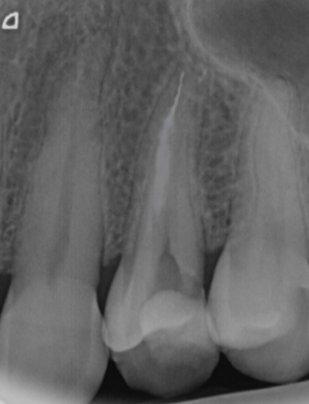

Post-OP X-Ray

Successfully removed file.

Broken file captured with the LassoTip Yellow (0.12 mm).